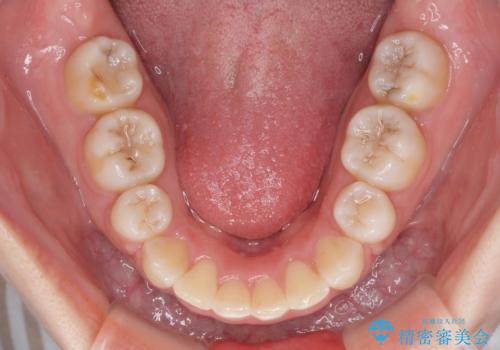

治療期間の目安は2年半~3年間でしたが、咬み合わせにより上顎装置が頻繁に脱落してしまい、治療期間が長期化してしまいました。

期間はかかったものの、口元の張り出し感や歯のデコボコが解消され、患者様には大変満足していただけました。